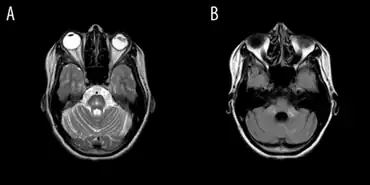

MRI of the brain may show characteristics of OPCA, such as specific changes in the size of affected parts of the brain. This is more likely as the disease progresses; it is possible to have OPCA and have a normal brain MRI (especially within the first year of symptom onset).